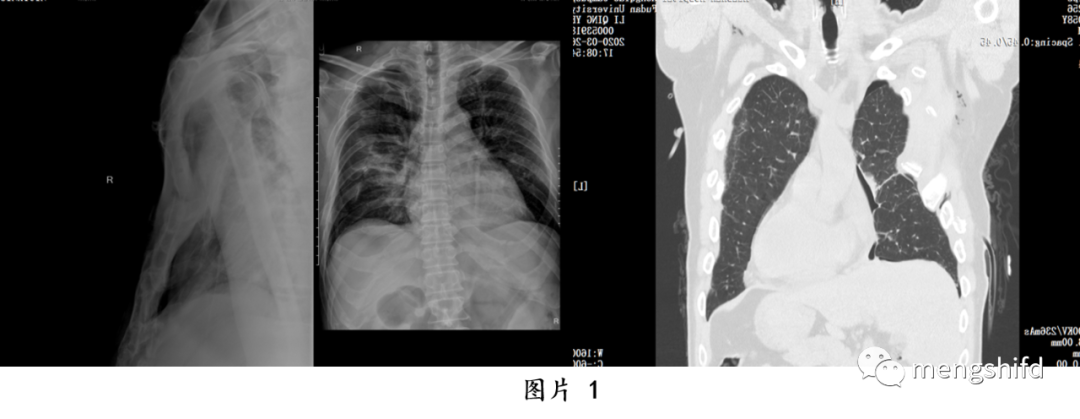

多发肋骨骨折和胸骨骨折合并连枷胸的手术治疗方法